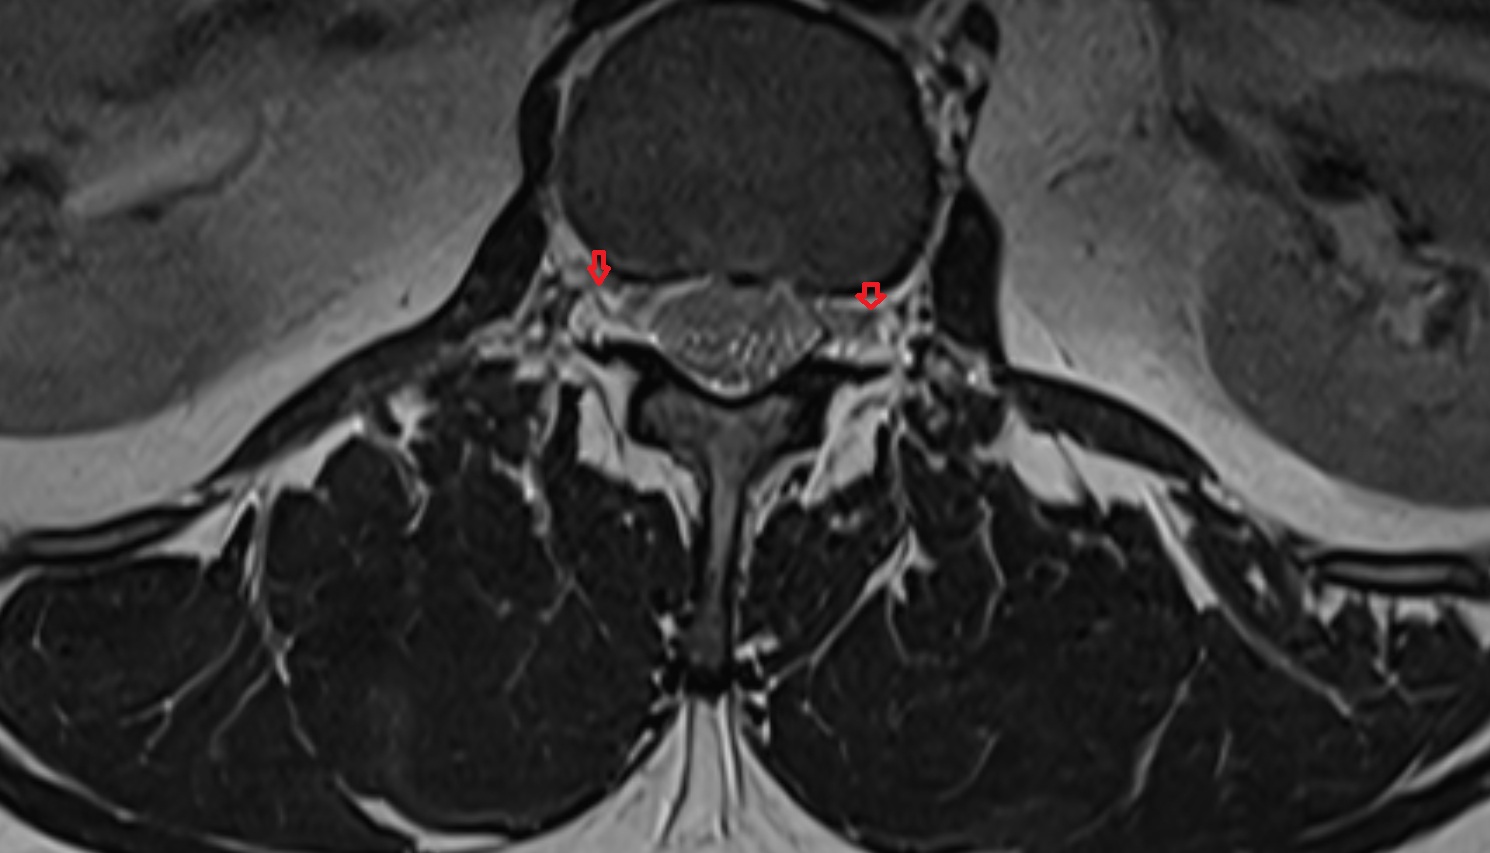

- Facet joint of vertebra (Zygapophyseal joints)

- Traversing nerve root of spinal nerve

- Exiting nerve root of spinal nerve

- Dorsal traversing nerve root

- Ventral traversing nerve root

- Dorsal exiting nerve root

- Ventral exiting nerve root

- Dorsal root ganglion of spinal nerve